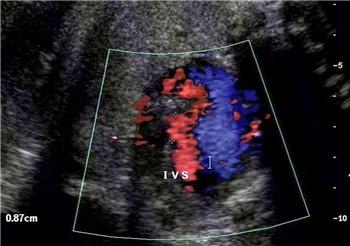

大千世界,无奇不有。最近,国外一个流浪孕妇在孕4月去医院产检时不幸发现胎儿心脏有缺陷,考虑到自己贫穷和居无定所,她痛苦地决定结束胎儿的生命。

谁也没用想到,她停止服药后,腹中的宝宝竟然茁壮成长,直到宝宝分娩,医护人员的检查结果让她简直不敢相信自己的眼睛,孩子非常完美健康,没有一点疾病,孕期检查出来的心脏缺陷和主动脉弓发育不全竟然“自我矫正”,不知什么时候不知不觉自愈了!医生也无法做出科学解释,只是说宝宝的心脏可能经历自我修复,他真的是个奇迹宝贝,是上帝送给流浪孕妇的礼物。

如果只是患有简单的先心病,出生后通过治疗是可以完全治愈的,还甚至出现某些胎儿母体内自愈的情况,但这类情况甚少见;宫内被确认的严重心血管病的胎儿,能够长期存活的极少。所以最好的还是孕期妈妈注意预防,注意饮食和及时产检。所以胎儿心脏有问题是否要流掉,最好征求医生专业意见。